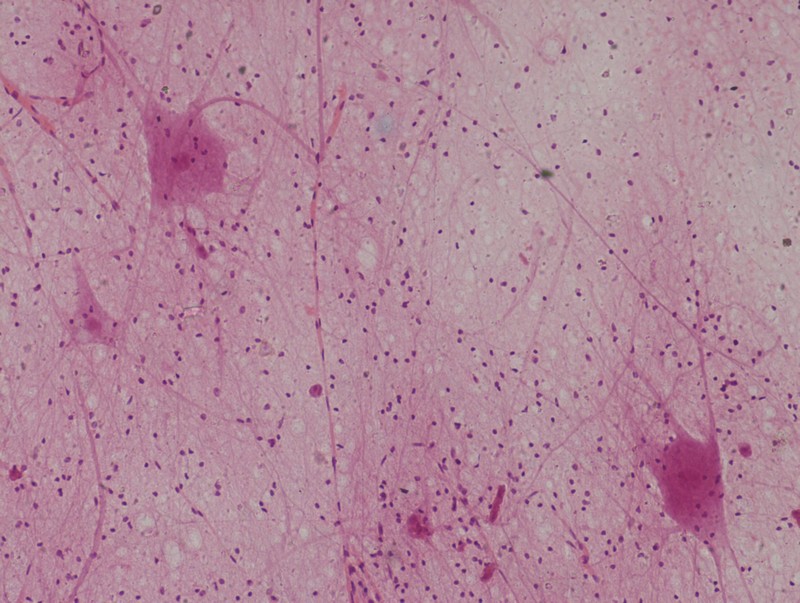

圖2:明場(chǎng)下的染色神經(jīng)元

和其他各種細(xì)胞一樣,神經(jīng)元幾乎是透明的,不能直接用明場(chǎng)觀察,為了滿足科教等應(yīng)用,可以用姬姆薩染色法等方式將神經(jīng)元處理成染色樣品,以便生物顯微鏡進(jìn)行明場(chǎng)觀察。

但這些處理會(huì)影響細(xì)胞活性,不適合動(dòng)態(tài)觀察。